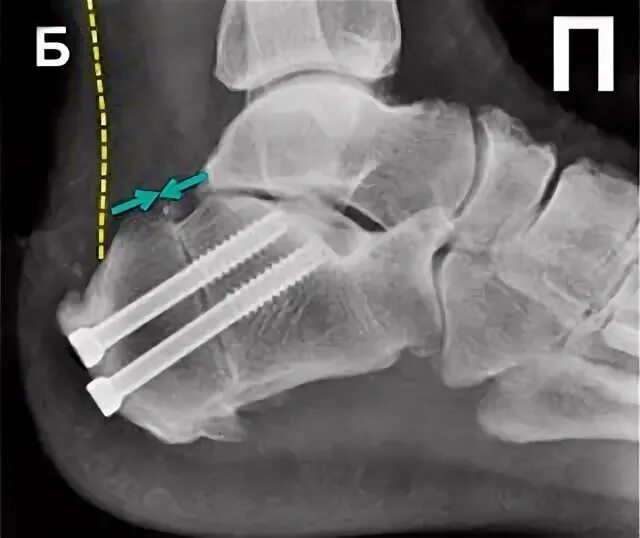

Пяточная остеотомия